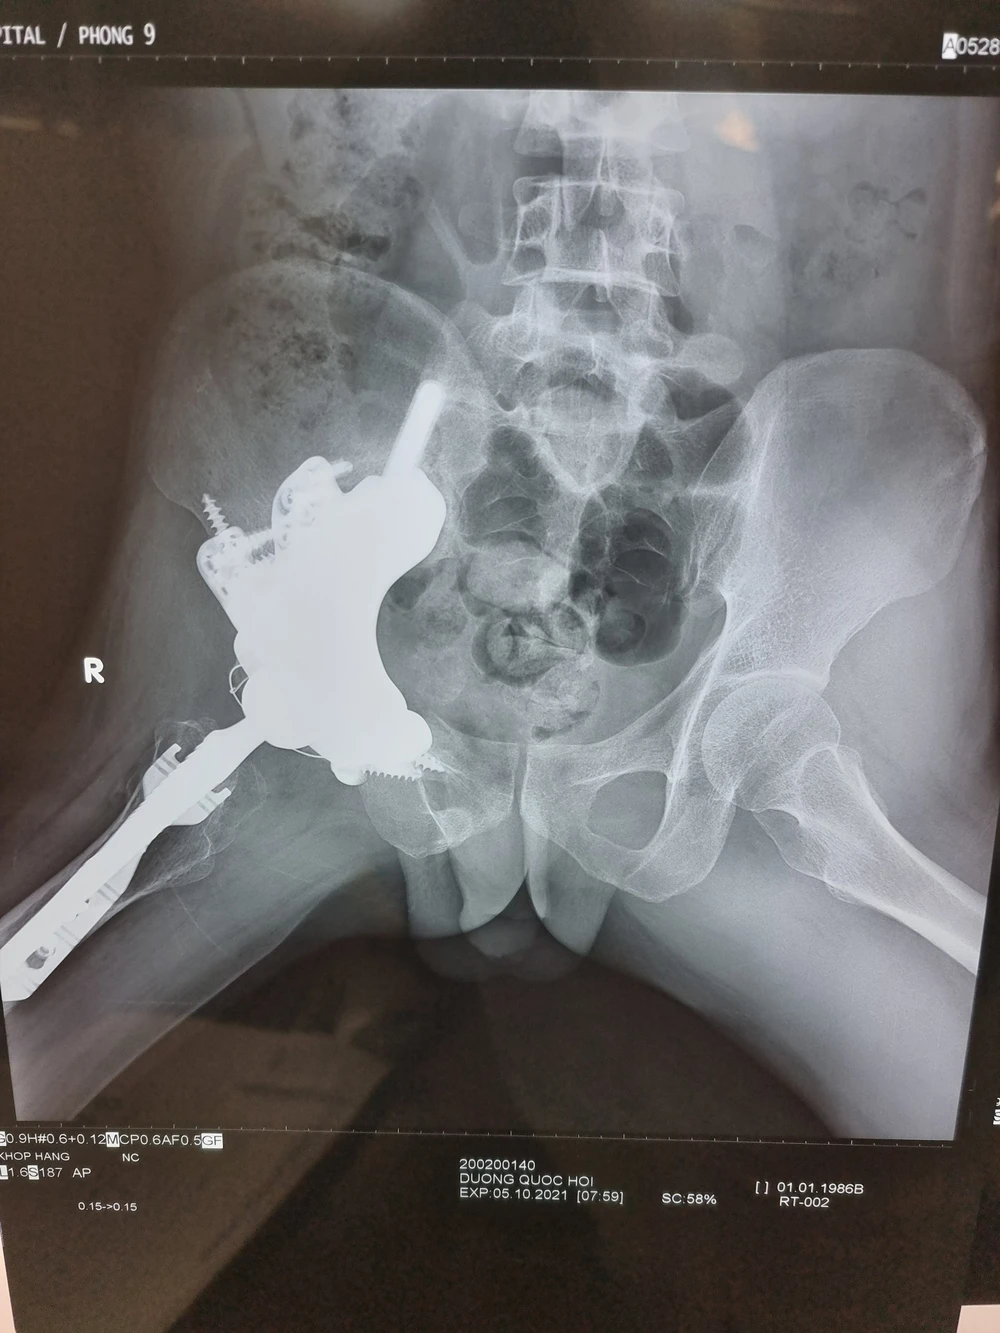

Phim chụp X-quang sau 3 tháng của bệnh nhân cho thấy xương phát triển tốt. Ảnh: BVCC

Bệnh nhân được theo dõi sát tình trạng sức khỏe trong hơn một tháng. Quá trình hồi phục của Hội diễn ra thuận lợi, xương phát triển tốt và dự kiến trong vài tháng tới, chàng trai trẻ có thể đi đứng bình thường, quay lại với công việc cùng những ước mơ dang dở trước đây.